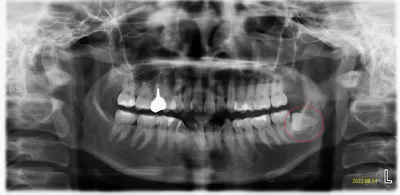

病人2023.12終於去拔了#38左下智齒,但今年冬天很濕冷,他開始又不舒服,忍了幾天,還是還找我?疑問智齒不是拔掉了嗎?為何還會作怪(讓人不舒服)?